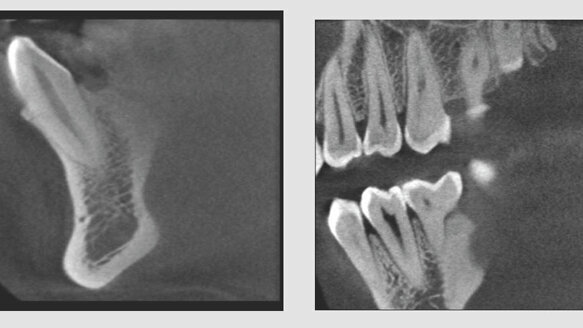

The Suni3D HD System has a 0.08 voxel size, among the elite voxel sizes currently in the industry, providing image definition and anatomical landmarks that cannot be seen by traditional 2-D imaging, according to Suni Medical Imaging. Suni3D HD is a perfect fit for endodontists and practitioners performing implants, Suni Medical Imaging says.

“Suni has always been interested in the specialized needs of endodontists,” said Paul Tucker, vice president of marketing. “The small field of view design is perfect for quadrant dentistry, while keeping radiation doses for patients at a minimum. The Suni3D HD system is one of the few systems on the market with a 5x5cm focused field of view, meaning lower doses of radiation for the patient and less liability for the doctor.”

The Suni3D HD system is perfect for capturing the necessary 3D anatomic structures for even the most demanding endodontic procedures. Suni3D HD optimizes the doctor’s practice while allowing them to provide the exceptional endodontic care that patients deserve, according to Suni Medical Imaging. The new 3-D-only system is also upgradeable to include a panoramic option should the practitioner decide to perform panoramic imaging in the future.